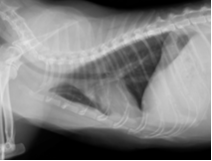

↑術後約1週間の胸部レントゲン

大きな手術でありましたが、約1週間の入院を経て無事に退院し、その後は通常通りの生活を送れています。この子のようにちょっと咳をするなどの軽い症状でも、意外と大きな病気が潜んでいることもあります。ただし、早期に病気を見つけてあげて早期に治療することで、良好な状態を維持することや完治を目指すこともできます。少しでも変わったことや気になることがあれば何でもご相談してください。